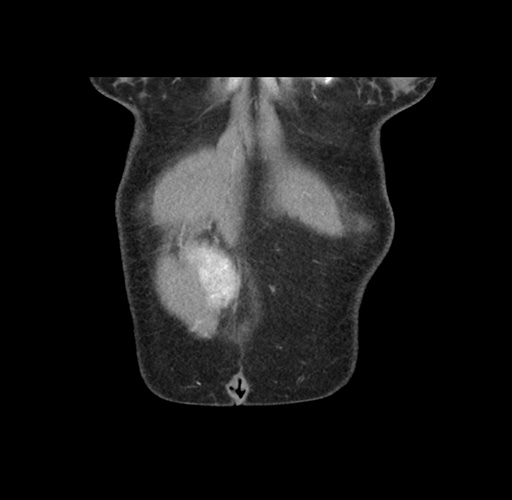

Imaging Analysis

Look through the patient's CT scan to identify any areas of concern for the necessary procedure.

Based on your CT findings, which issue(s) would give reason for "planned slowing down moment(s)" in this case?